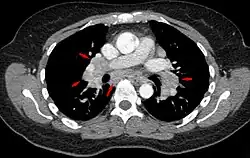

Chest radiograph changes are divided into four stages:[104]

- bihilar lymphadenopathy

- bihilar lymphadenopathy and reticulonodular infiltrates

- bilateral pulmonary infiltrates

- fibrocystic sarcoidosis typically with upward hilar retraction, cystic and bullous changes

Although people with stage 1 radiographs tend to have the acute or subacute, reversible form of the disease, those with stages 2 and 3 often have the chronic, progressive disease; these patterns do not represent consecutive "stages" of sarcoidosis. Thus, except for epidemiologic purposes, this categorization is mostly of historic interest.[28]

Hilar adenopathy especially on the person's left (AP CXR)

Hilar adenopathy especially on the person's left (lateral CXR)

Hilar adenopathy especially on the person's left (coronal CT)

Hilar adenopathy especially on the person's left (transverse CT)